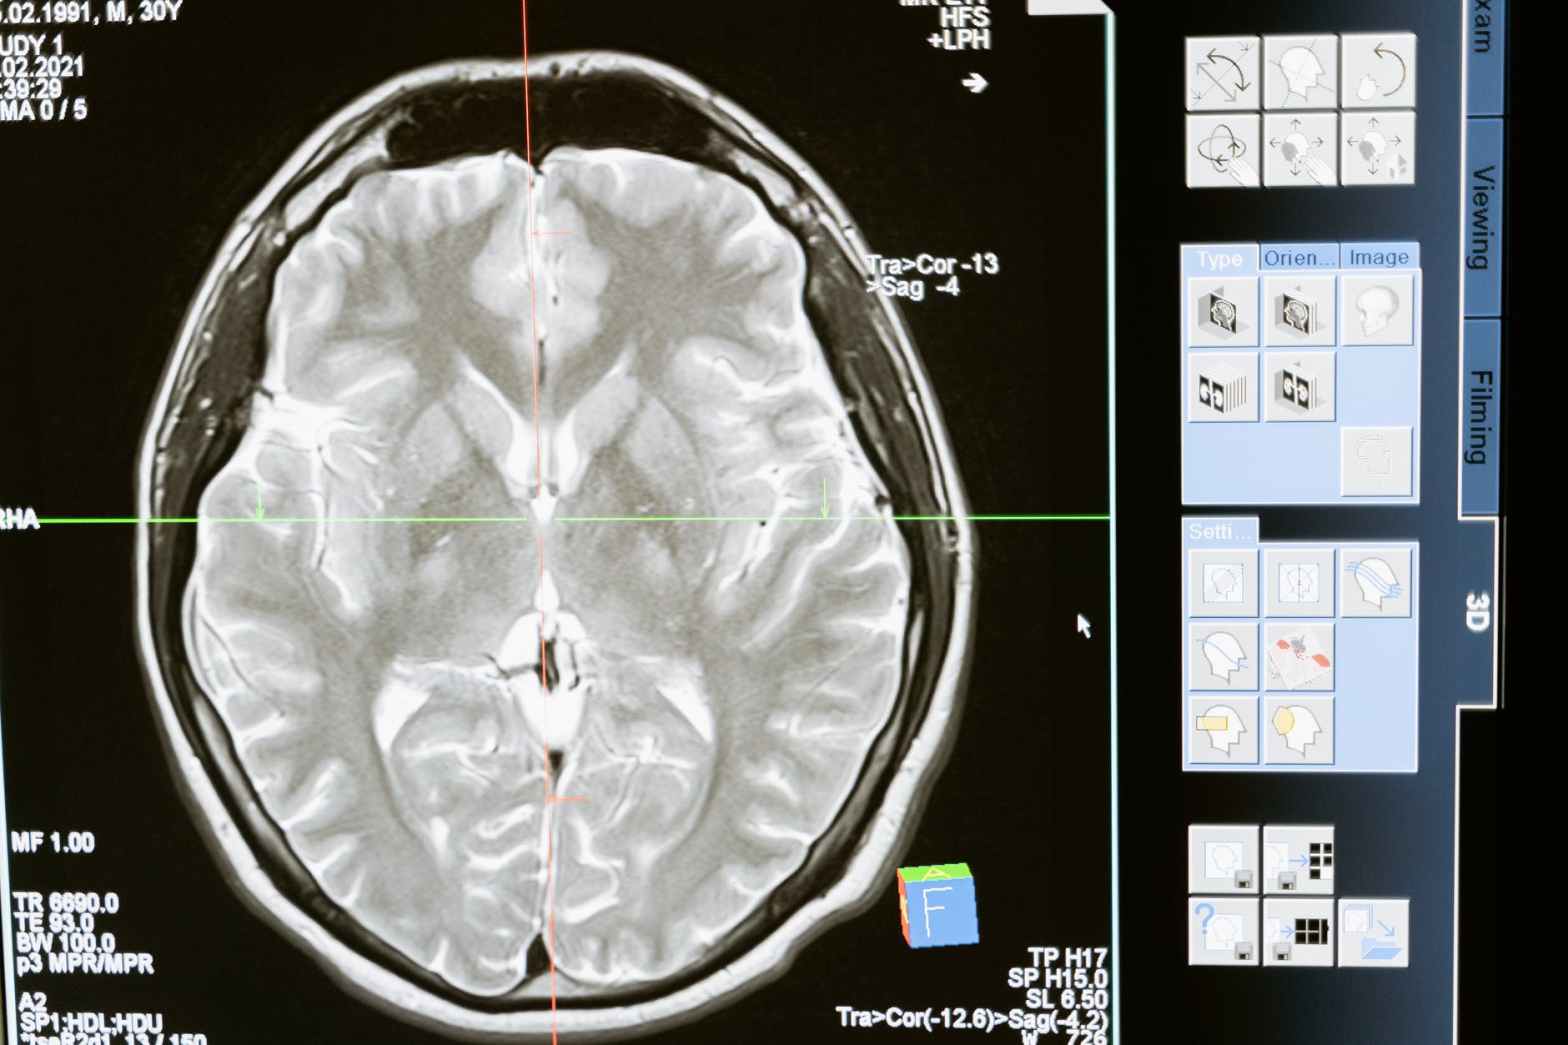

Resonancia magnética para el cáncer

La IRM (también conocida como imágenes por resonancia magnética, resonancia magnética, RM e imágenes por resonancia magnética nuclear [RMN]) ayuda a los médicos a detectar el cáncer en el cuerpo y buscar signos de que se ha propagado. La resonancia magnética también puede ayudar a los médicos a planificar el tratamiento del cáncer, como cirugía o radiación. La resonancia magnética es indolora y no tiene que hacer nada especial para prepararse para esta prueba. Pero es muy importante que informe a su médico y al tecnólogo (la persona que realiza la prueba) si tiene algún metal en el cuerpo.

¿Qué muestra la resonancia magnética?

La resonancia magnética crea imágenes transversales de su interior. Pero la resonancia magnética usa imanes potentes para generar las imágenes, no radiación. Una resonancia magnética toma cortes transversales (vistas) desde muchos ángulos, como si alguien estuviera mirando un corte de su cuerpo desde el frente, desde el costado o desde arriba de su cabeza. La resonancia magnética crea imágenes de partes de tejido blando del cuerpo que a veces son difíciles de ver con otras pruebas de imágenes.

La resonancia magnética es muy buena para encontrar y señalar algunos tipos de cáncer. Una resonancia magnética con medio de contraste es la mejor manera de ver los tumores cerebrales y de la médula espinal. Mediante la resonancia magnética, los médicos a veces pueden determinar si un tumor es o no cáncer.

La resonancia magnética también se puede usar para buscar signos de que el cáncer puede haber hecho metástasis (diseminación) desde donde comenzó a otra parte del cuerpo.

Las imágenes de MRI también pueden ayudar a los médicos a planificar tratamientos como cirugía o radioterapia.